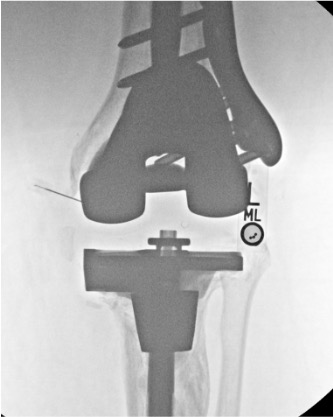

Post-Arthroplasty

Finding

Significance

Contrast tracking along prosthesis-bone interface

Loosening (confirm with delayed fluoroscopy; contrast should clear in intact prosthesis)

Fistulous tract to adjacent soft tissue

Periprosthetic infection — aspirate joint fluid for culture before injecting contrast

Communication with adjacent joint or bursa

Erosion of joint capsule

Post-arthroplasty arthrogram uses iodinated contrast only — no gadolinium. Joint aspiration should precede contrast injection when infection is suspected; send fluid for cell count, Gram stain, culture, and crystal analysis.